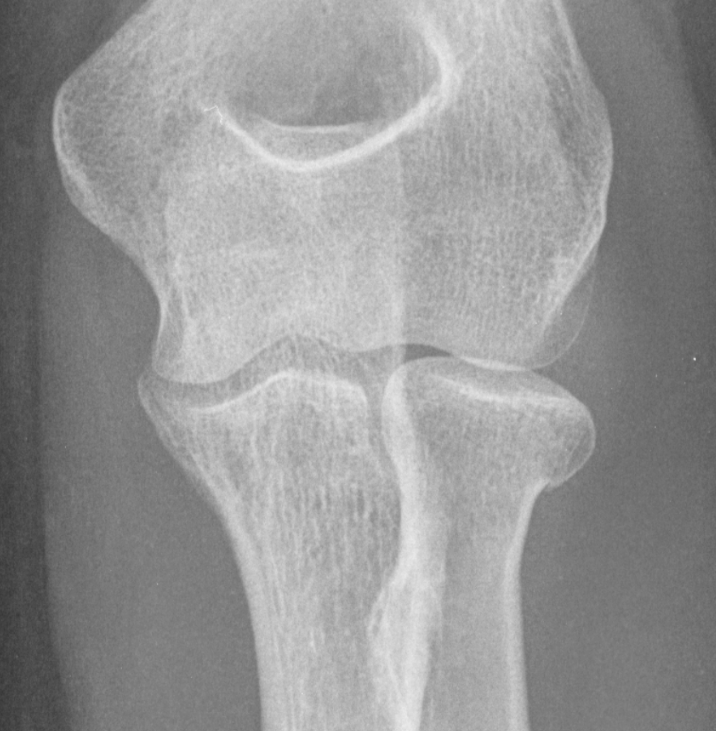

3. Radial neck fracture